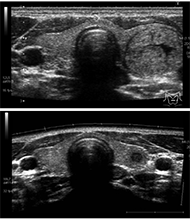

A thyroid adenoma in a pubertal male with thyroxine-binding globulin deficiency もっと読む

編集者のコメント

(Upper) Thyroid ultrasonography revealed a nodule measuring 14 × 12 × 19 mm with clear borders in the left lobe of the thyroid gland accompanied by cystic degeneration and calcification without increased blood flow or surrounding lymphadenopathy.

(Lower) The nodule shrank to 5 × 5 × 6 mm without any treatment six months after fine-needle aspiration cytology (FNAC).